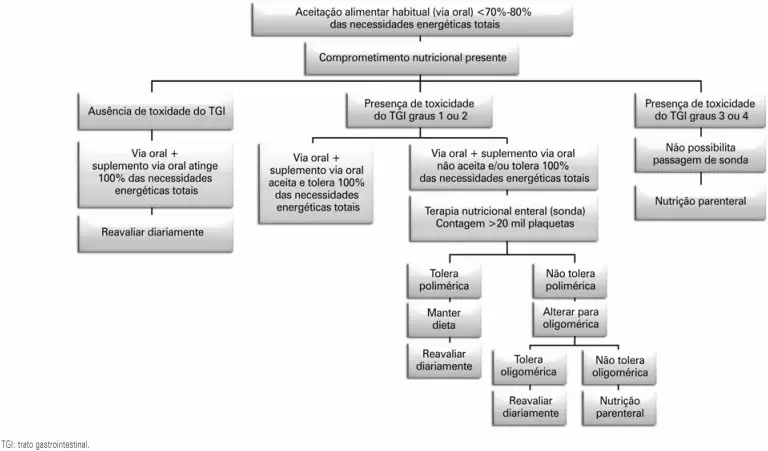

RESUMO O Consenso Brasileiro de Nutrição em Transplante de Células-Tronco Hematopoiéticas: crianças e adolescentes foi elaborado com a participação de nutricionistas, médicos nutrólogos e médicos hematologistas pediátricos de 10 centros brasileiros que são referência em transplante de células-tronco hematopoiéticas. O objetivo foi salientar a importância do estado nutricional e da composição corporal durante o tratamento, bem como as principais características relacionadas à avaliação nutricional do paciente. As intenções, ao se estabelecer o consenso, foram aprimorar e padronizar a terapia nutricional […]